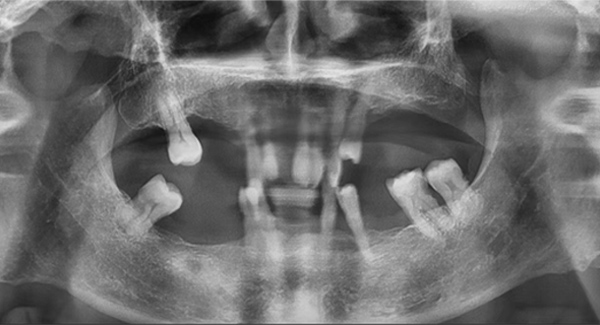

另一个全口种植案例,除了缺牙、骨量等常见问题外,他的咬合还是内倾的深覆合,这是最大的治疗难点。也就是说,患者的咬合不正常,如果按常规的思路种植后直接戴临时牙冠,当他半年后戴上最终牙冠时,整个咬合可能不会理想,到那个阶段再去调整咬合,效果可能不太好,人也比较受罪。

我决定做难但正确的事情。种植手术完成后,我让患者戴上了树脂义齿重建咬合,让他通过日常的咀嚼,在原本平整的下牙义齿上慢慢形成新的尖窝对应关系。前后花了半年时间,才达到稳定且可重复的咬合状态。这时候,再制作第二幅临时义齿,也就是有解剖牙尖和尖窝交错关系的临时牙,让患者再次适应咬合3个月。最后,我把患者适应并且满意的咬合关系转移到他的最终牙冠上,完成了修复治疗。

这位患者不到60岁,但由于后牙全部缺失多年,残留的前牙已松动且上下无法接触,他基本没办法正常咀嚼,人非常消瘦。完成治疗后我跟踪了这个病例一年,从前后对比照片可以看出,能正常吃东西后他的脸上渐渐也有肉了。